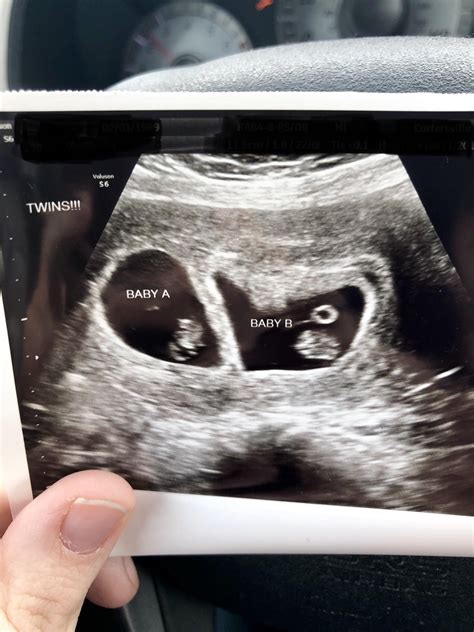

• Confirmation of Twins: The technician will look for two separate gestational sacs, each containing an embryo. This confirms the presence of twins.

• Type of Twins: Identical twins share a single placenta and amniotic sac, while fraternal twins have separate placentas and amniotic sacs. The ultrasound can help determine the type of twins.

• Heartbeat Detection: At 8 weeks, the embryos' heartbeats should be detectable. The technician will listen for two distinct heartbeats to ensure both embryos are developing normally.

• First Ultrasound: The 8 Week Ultrasound Twins scan is a significant milestone. Celebrate this moment by capturing images and sharing the news with loved ones.